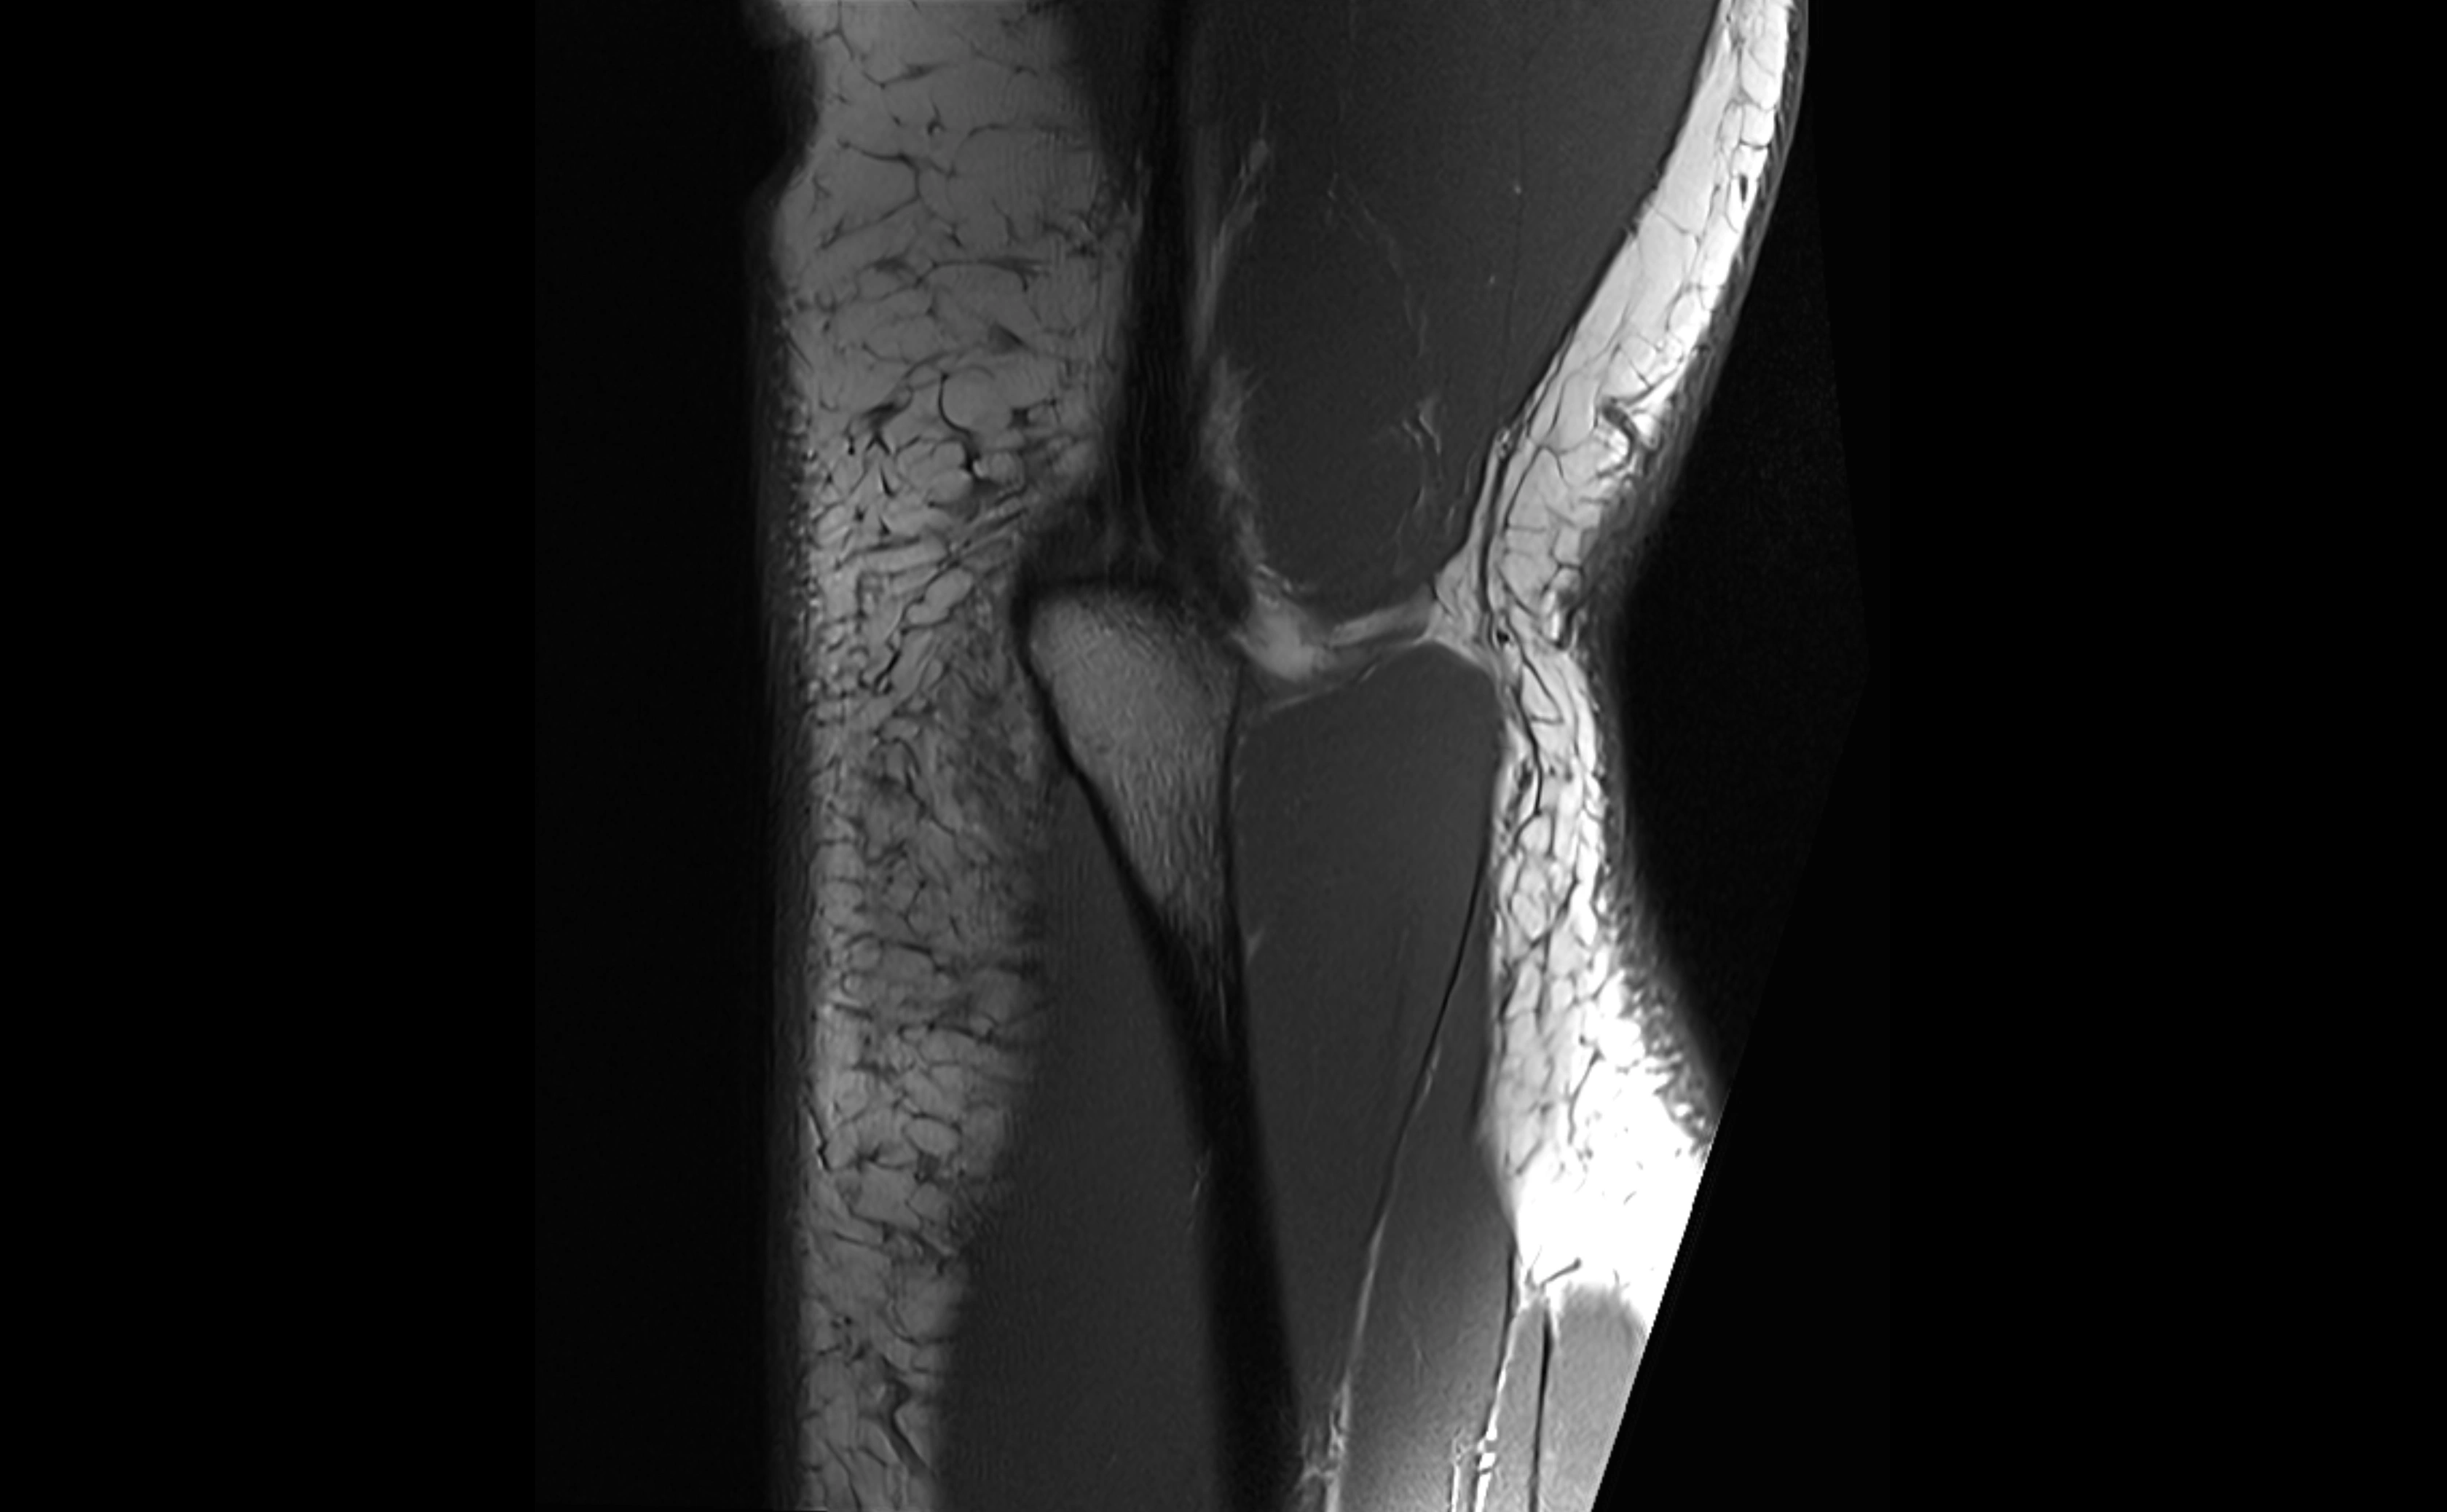

MRI Appearance

T1-weighted images:

• Ligament: low signal intensity (dark), appearing as a continuous band around the radial head.

• Adjacent fat and marrow: bright, creating contrast with the ligament.

• Thickening or disruption indicates injury or fibrosis.

• Joint capsule and synovium seen as thin low-signal lines contiguous with ligament margins.

T2-weighted images:

• Ligament: low signal (dark) with clear delineation from joint fluid.

• Fluid or edema: bright hyperintense, separating or surrounding the ligament in partial tears.

• Complete tear: discontinuity or non-visualization of ligament fibers, often with joint effusion.